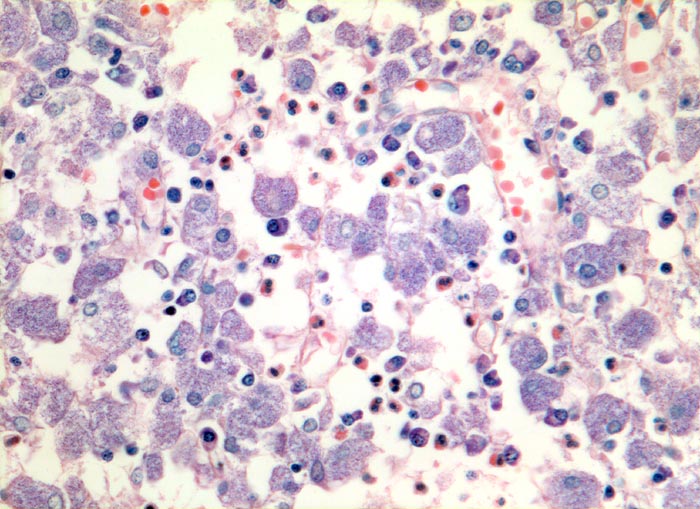

atypische Mykobakteriose (Mycobacterium avium intracellulare)

Grossleibige histiozytäre Zellen mit fein granuliertem Zytoplasma. Daneben wenig Plasmazellen und Granulozyten.

Ziehl-Neelsen Färbung: die Histiozyten sind voll von säurefesten Stäbchen.

Seit 3 Jahren HIV positiv.

Das Bild der mykobakteriellen Histiozytose wird vor allem durch atypische Mykobakterien verursacht, vereinzelt aber auch durch Mykobakterium tuberculosis.

320